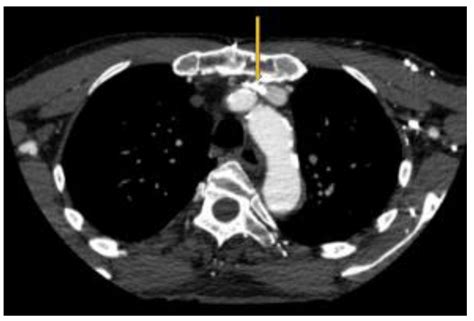

Syndrome Sinistre: Left Brachiocephalic Vein Compression and its ...

preprints.org